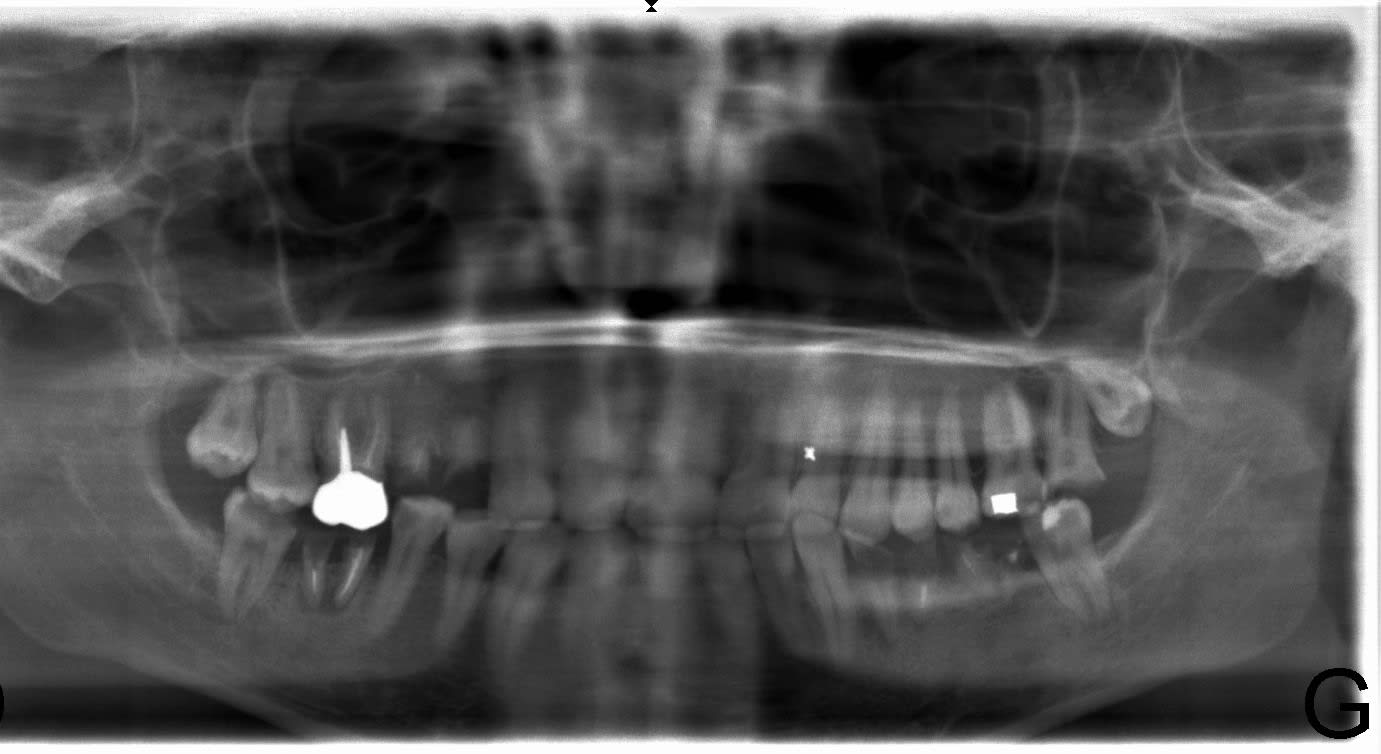

Quand je dis 2 , 3 par semaine ,c 'est plutôt 1 par jour ,allez quel âge ? .... Cmu que je vois depuis juin avec des interruptions ...sérieuse , pas de problème .

Ah oui pour carident , l'export en jpeg n'est pas top ! pano Morita .